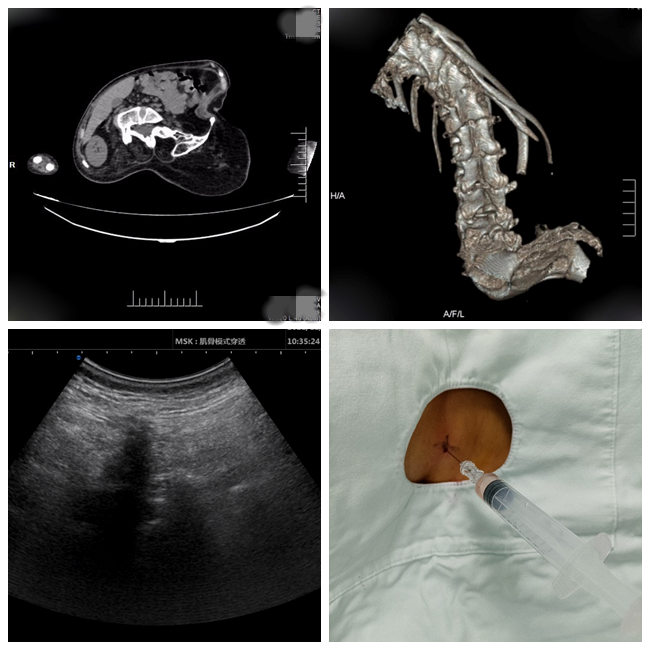

(左上:CT示脊柱严重畸形;右上:CT三维重建示脊柱重度侧弯;左下:超声辅助腰椎穿刺;右下:成功进行腰穿注药)

2021年,诺西那生钠作为治疗SMA的靶向药物进入罕见病医保目录,给更多SMA患者带来了希望,越来越多的SMA患者可以通过这种药物延缓疾病进展,改善生活质量。20出头的小邹也是受益者之一,但小邹因长期患病导致目前全身只有几根手指能动,更无法站立、行走,每日需依靠无创呼吸机呼吸十余小时。小邹脊柱侧弯严重,实现诺西那生钠腰椎穿刺鞘内注射给药是一个巨大的挑战。麻醉科罗剑刚主治医师通过超声引导技术,结合脊柱脊髓影像学检查,寻找穿刺间隙,设计穿刺路径,于3月4日顺利为小邹完成鞘内注射,也点燃了他心中对未来的希望。小邹给罗剑刚医师写来一封饱含深情感谢信,字里行间流露出的对生命的渴望和对完成治疗的惊喜,令人非常感动。

据介绍,伴有严重脊柱侧弯的脊髓性肌肉萎缩症(SMA)患者收治在儿科和神经内科,在靶向药治疗过程中需要在严重畸形的腰椎上穿刺,实现鞘内注药难度和风险极高。在兄弟学科的要求下,麻醉学科迎难而上,在麻醉手术部王锷主任和鄢建勤教授支持下,罗剑刚主治医师运用多种影像技术辨识与正常结构迥异的鞘内穿刺路径,解决了这类患者无法注药的难题,不仅获得百分之百的操作成功率,而且无一例并发症,已经使十多位复杂脊柱畸形的SMA患者和家庭重燃新生的希望。这也是麻醉手术部通过引入超声、DSA和CT引导技术并应用于临床麻醉和疼痛诊疗,取得的一系列临床新技术成果之一。